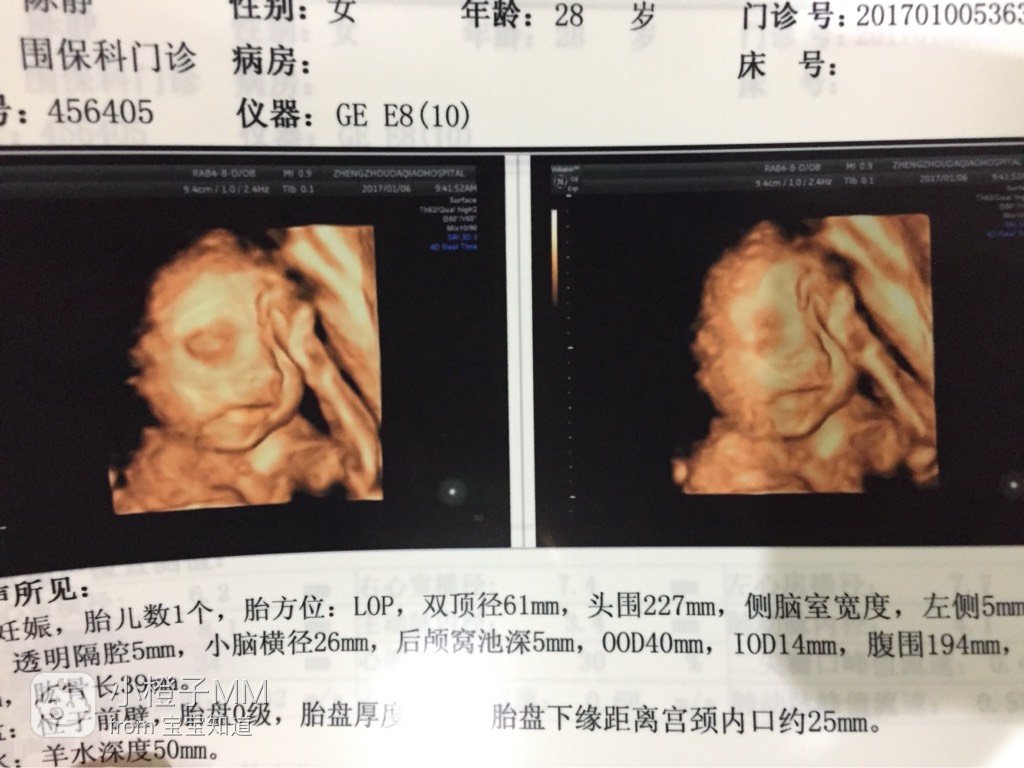

宝宝8岁10个月7天 LV.7你胎盘也有点低吧!

孕40周+0天 LV.6是啊!医生说这样生的时候容易出血!不过医生又说看看后期能长上来不能!我也不懂!

138*****830_Rjpu:你胎盘也有点低吧!

2个宝宝 LV.6会长上去吗??我也是胎盘低。。对此能否长得上去,我半信半疑

小橙子MM:是啊!医生说这样生的时候容易出血!不过医生又说看看后期能长上来不能!我也不懂!

孕40周+0天 LV.6说28周以后就定型了!28周以前可能长上去!

訫怡心缘:会长上去吗??我也是胎盘低。。对此能否长得上去,我半信半疑